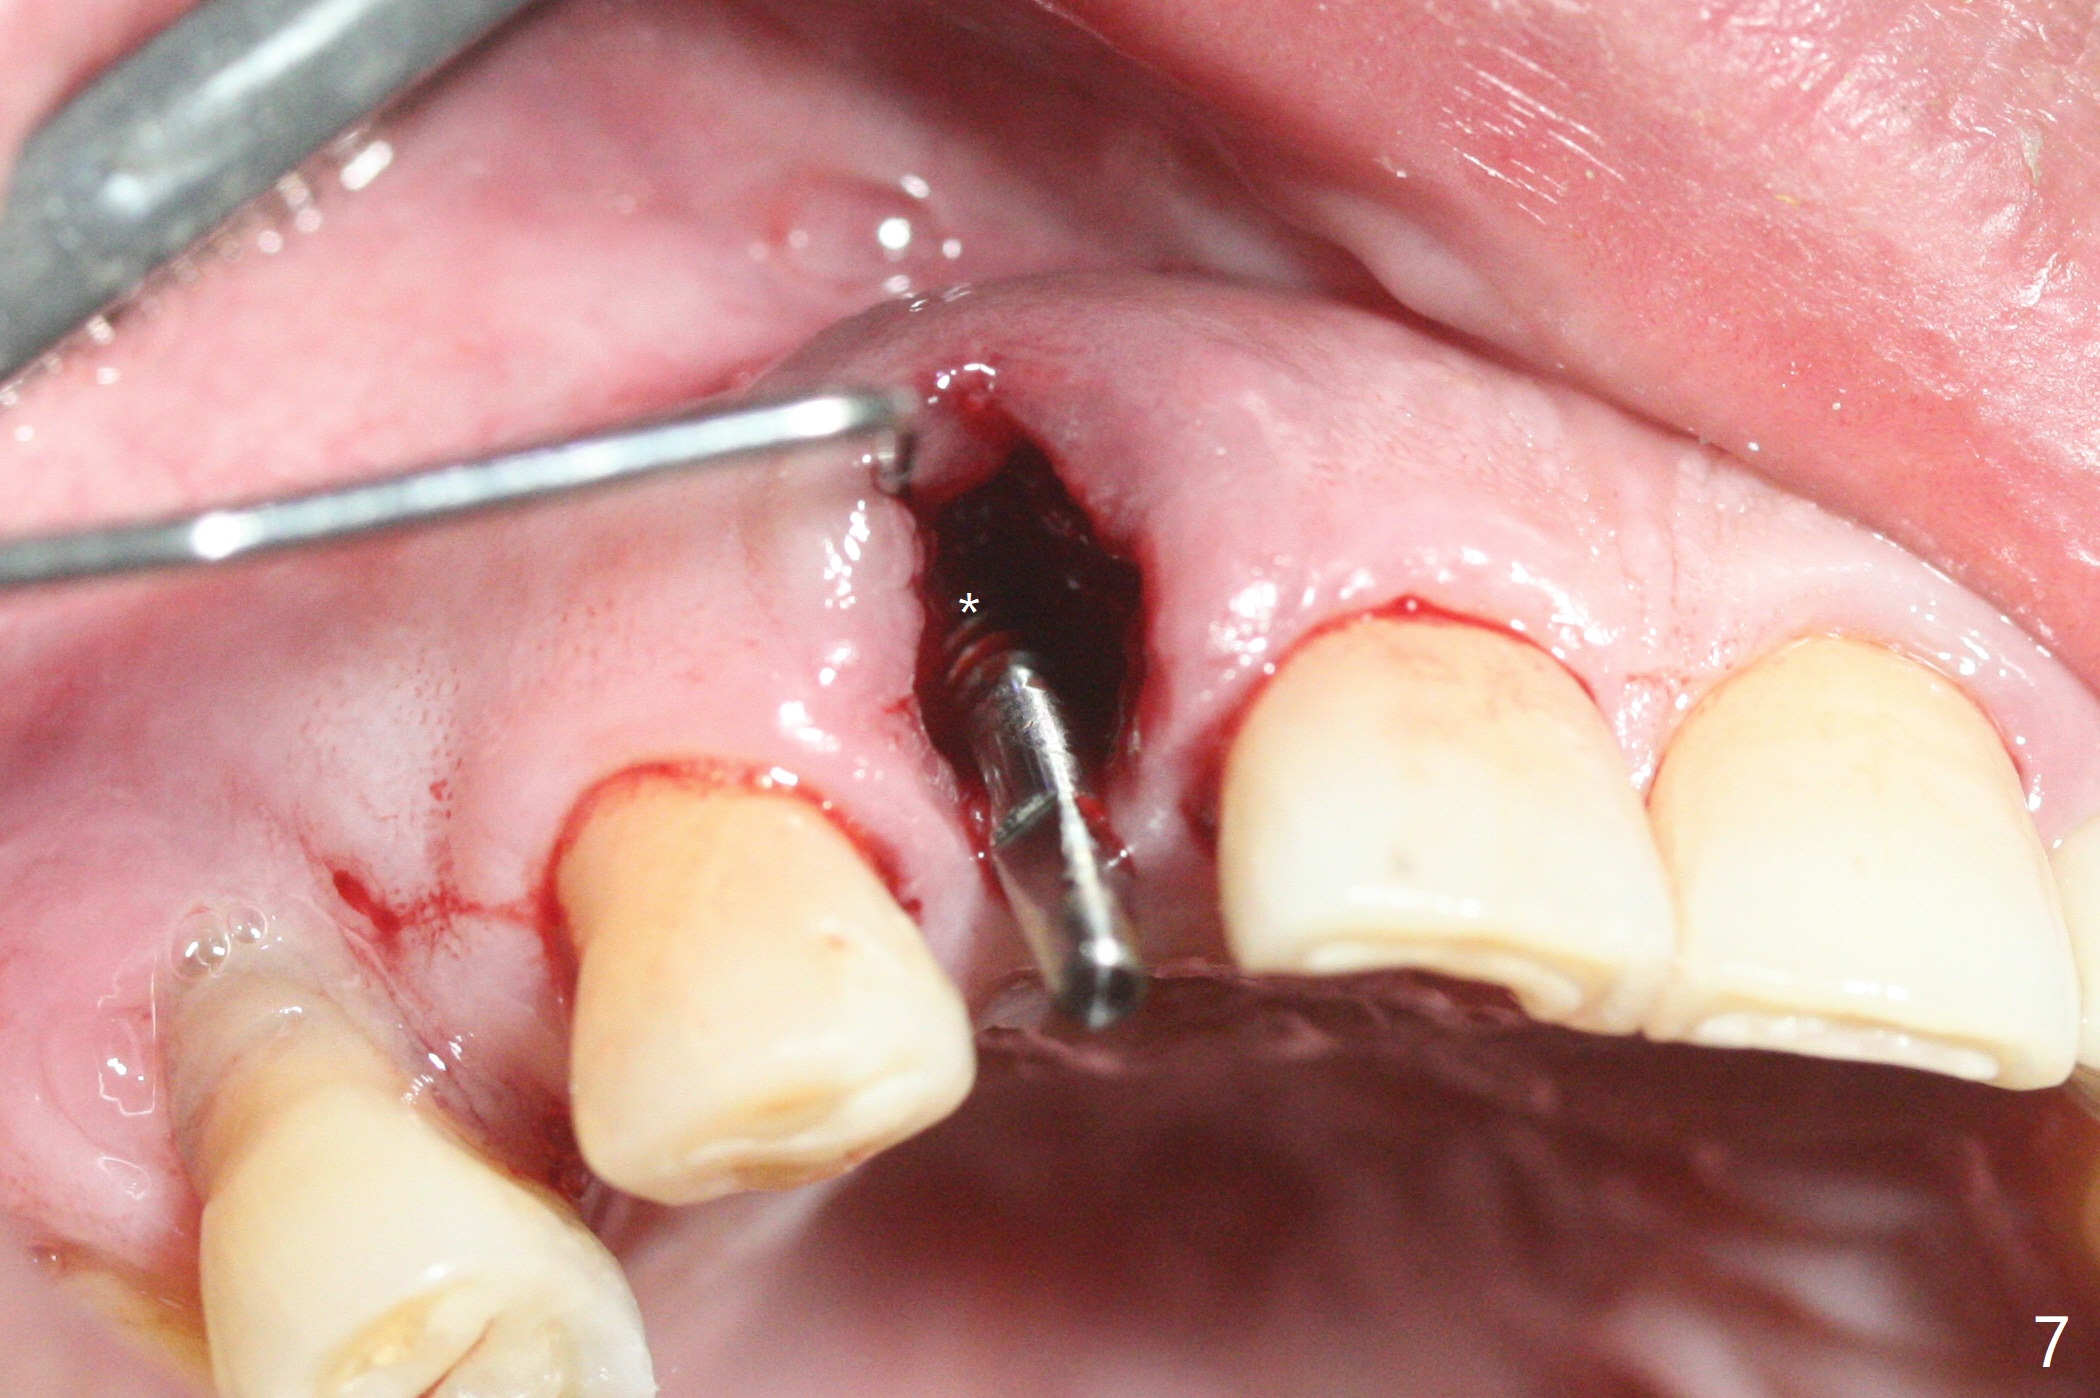

68岁男士右上2严重骨质吸收,颊侧骨板缺失,术前牙龈退缩也十分明显(图一,二),术中对脆弱牙龈缘(图三:*)不应施加任何压力或者牵拉,更不能切开,保持最佳血供。按照术前设计,在牙槽窝腭侧钻洞(图四),植入2.5x15毫米一段式植体(扭力>35Ncm),基台特长(牙龈厚,图五)),基台位于合适修复位置(图六),4-5毫米螺纹颊侧暴露(图七:*)。植骨(图八(CT冠状切面(拔牙后:黑色)):箭头)前,将PRF膜(白线)一头(a)插入牙槽窝颊侧,另外一头(图八,九:b)放置颊侧牙龈颊侧。然后填入粘性骨粉(图九:S;图十四:*),将b头PRF膜往下翻,它末端事先冲一个洞(punch a hole using sterilized rubber dam punch),插入基台(图十(粉红色),十一),这样PRF膜不移位,牢靠地固定骨粉(图十(红圆圈),图十四:*),最后使用树脂敷料覆盖伤口(图十二,十三:A),同样需要基台(箭头,也就是一段式植体)固定,也就是没有即刻植体,就没有骨粉固位。术后两个月伤口缩小,肉芽组织生长(图十五)。撤除树脂敷料后,制作临时牙冠,半个月后唇侧植体有些暴露(图十六),嘱咐强化口腔卫生。